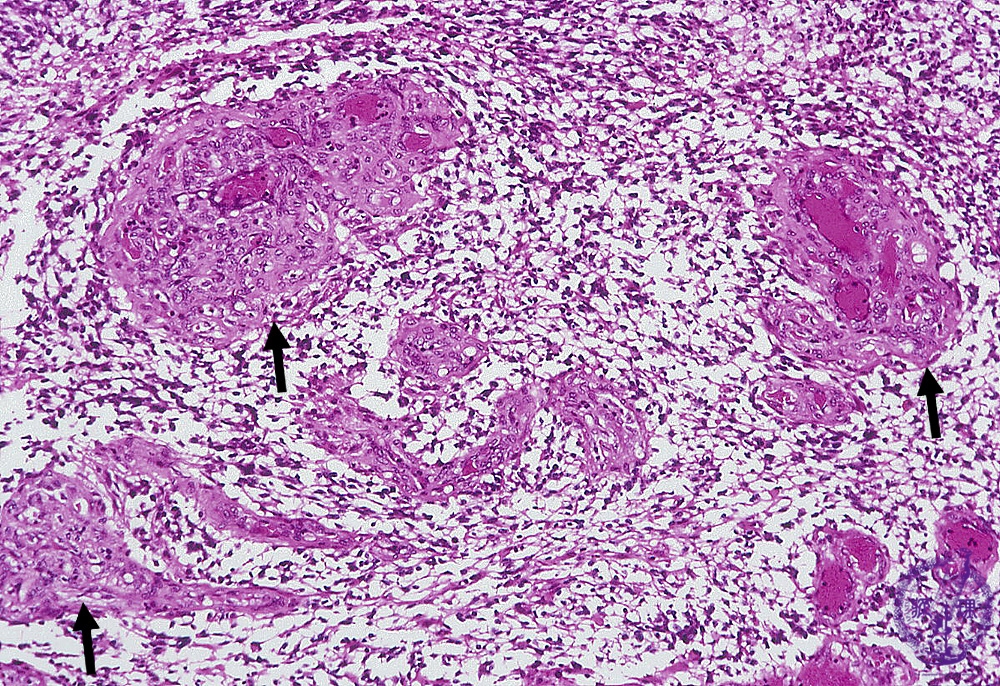

- ★(8)Glioma(Glioblastoma)

Microscopic findings (H.E. middle magnification): There were increased number of vessels with anintravascular proliferation of endothelial cells and thickening of the vascular wall (arrows). Sometimes, several vascular lumina were detected in a single vessel, also termed ‘glomeruloid structure’.